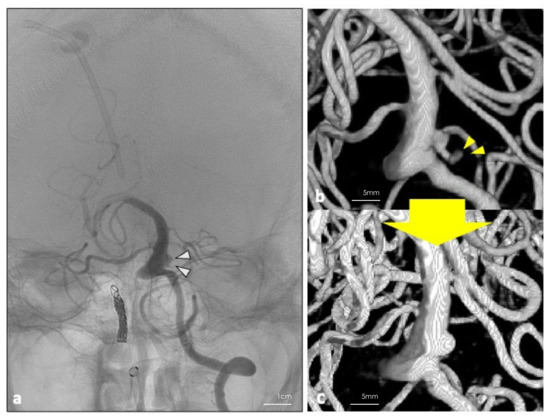

Figure 3.

(a) DSA was performed 26 days post operation. White arrowheads show the residual blood flow in the aneurysm. (b,c) Three-dimension reconstruction of the digital subtraction angiography performed 7 days before and 26 days after the operation. Disappearance of the bleb (yellow arrowheads) and shrinkage of the residual blood flow inside the aneurysm were achieved.

The patient’s postoperative plain CT showed no additional hemorrhages, and DSA revealed a disappearance of the bleb of the aneurysm (Figure 3a). Although he did not have any new neurological deficit, MRI showed a DWI high lesion in the left posterior inferior cerebellar artery (PICA) territory. No arterial sacrifice was made during the surgery. Thus, the cause of the infarction could be due to thrombus formation around the inserted catheter. After undergoing ventriculoperitoneal shunting, his consciousness disturbance level gradually improved during the course without re-rupture of the aneurysm. On the 26th day after the surgery, follow-up DSA revealed disappearance of the bleb and a remarkable shrinkage of the residual blood flow inside the aneurysm (Figure 3b,c). On the 72nd day after the onset of SAH, the patient was transferred to a long-term care hospital. His final follow-up mRS was 5.